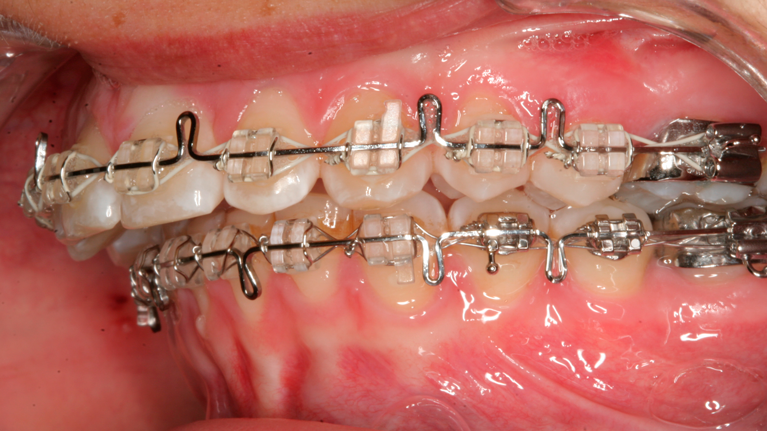

Til konferencen møder du en kirurgisk specialtandlæge fra Kæbekirurgisk Afdeling, muligvis en uddannelsestandlæge og en bøjletandlæge. De fremlægger den foreløbige behandlingsplan, som de forinden har udarbejdet. Du har mulighed for at få uddybet eventuelle spørgsmål til behandlingsplanen.